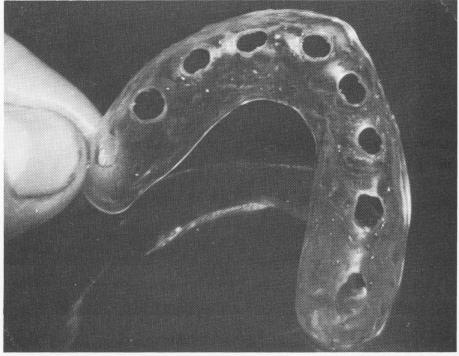

mouth for esthetics and proper bite. When these were satisfactory, the denture was processed (Fig. 10-212). The teeth were made of acrylic instead of porcelain. Holes were made inside the denture to coincide where the terminal ends of the triplant pins were to extend out of the fibromucosa. A clear, color-Iess acrylic template was also processed (Fig. 10-213) . This too had predetermined holes that coincided with the areas for the triplant pin insertions and with the holes inside the denture.

1 Prefabricated palateless denture with holes for pin implants

2 Colorless palateless acrylic template with holes for maxillary arch